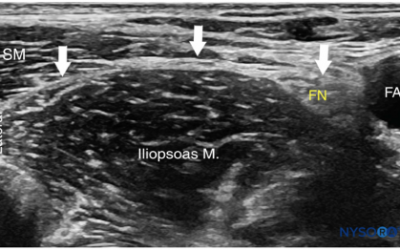

Hip Fractures and the Battle of the Blocks: SIFI vs IIFI

Hip fractures are a common emergency department presentation and, with an aging population, their incidence will continue to rise. These injuries are profoundly painful, and many patients experience moderate to severe pain for at least one month following fracture...